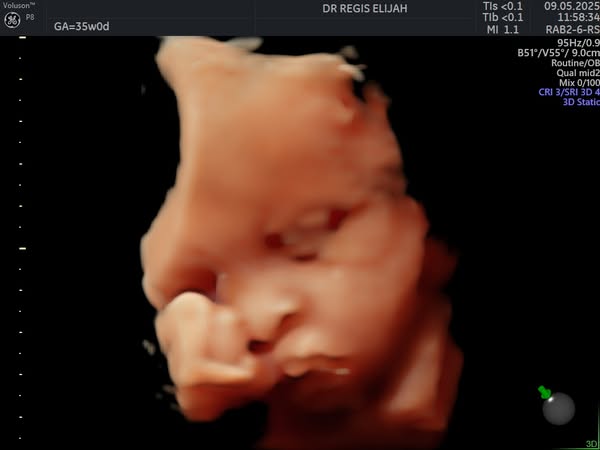

There’s nothing more magical than seeing your baby for the first time—and with our advanced 4D ultrasound technology, you don’t have to wait until delivery day to witness those precious moments!

At Elijah R OBGYN Women’s Clinic, our 4D pregnancy scans allow expectant parents to view their baby’s movements, facial expressions, and little kicks in real time, creating a powerful bonding experience.

🔸 Capture beautiful real-time images

🔸 Detect and monitor fetal development